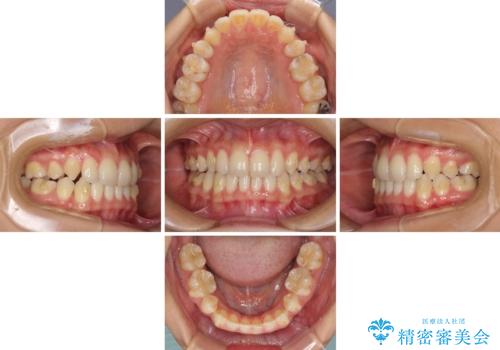

- 以前の矯正治療の後戻りにより、上の前歯にスペースができたことを気にして来院された患者様です。

インビザラインを用いて前歯のスペースを閉じつつ、上下の咬み合わせを構築していくこととしました。

隙間の空いてしまった前歯は、矯正治療で治療を行っても後戻りが起こりやすい傾向にあります。

マウスピースの保定装置をしっかりと装着しても空いてしまうため、細いワイヤーによる保定を併用することで後戻りを防止しています。